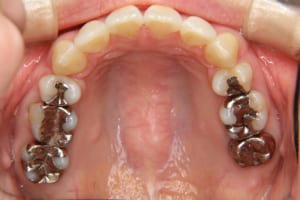

上下顎前突を伴う叢生の医療関係者の方の治療例

治療前

| 主訴 | 上の前歯が出ている |

| 治療内容 | リンガルブラケット(舌側矯正/裏側矯正)を使用した成人矯正治療を行いました。 |

| 使用した装置 | リンガルブラケット 歯科矯正用アンカースクリュー(2本) 筋機能訓練(MFT)は行っていません |

| 抜歯および非抜歯 | 上の左右第一小臼歯、右側第三大臼歯(親知らず) 下の左側第二小臼歯、右側第一小臼歯、左右第三大臼歯(親知らず) |